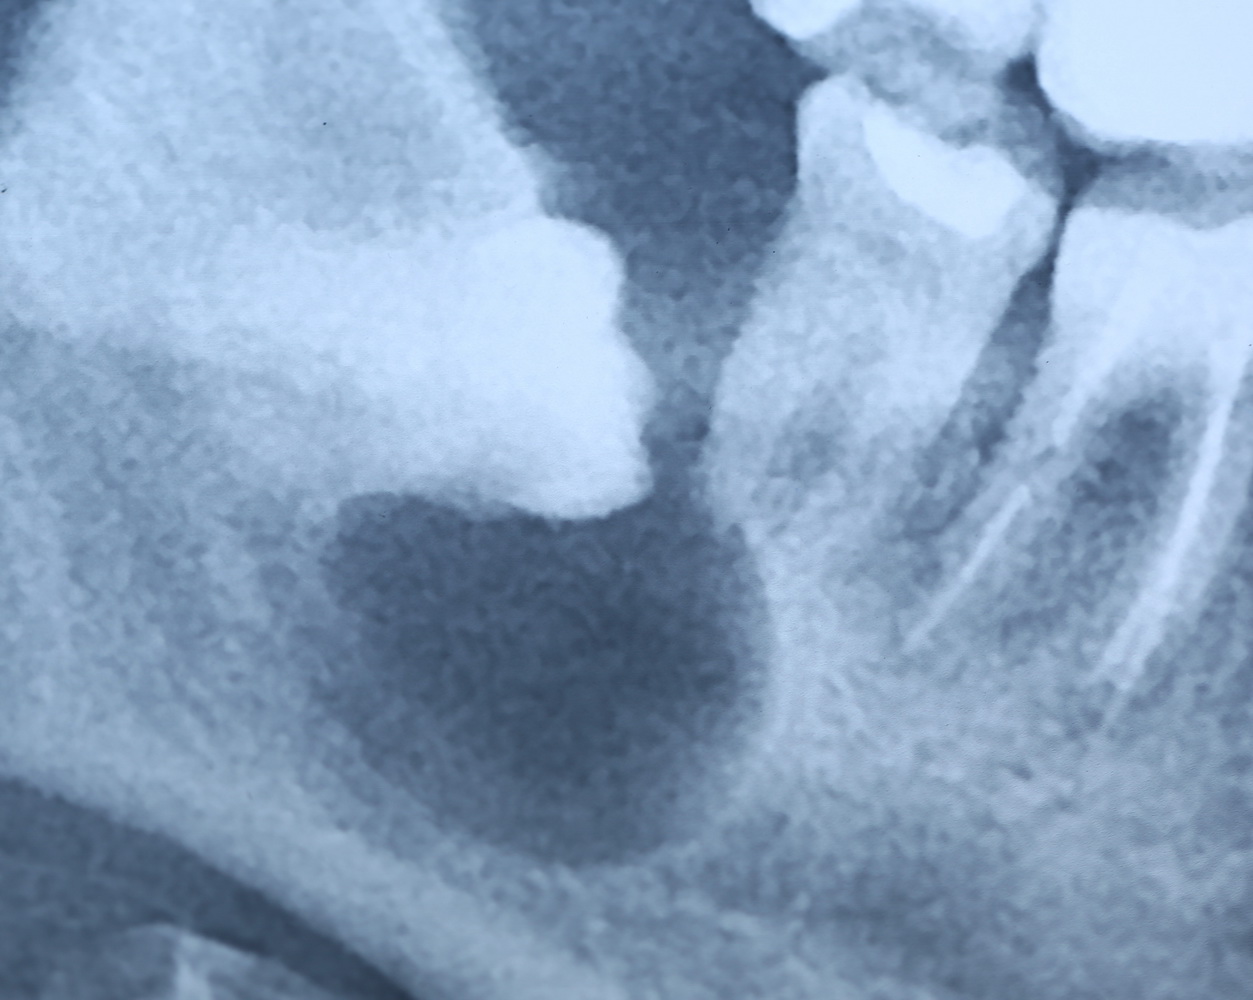

Давайте еще раз посмотрим на снимок:

Что мы на нем видим? Ну да, есть два лишних зуба.

К сожалению, мы не можем по ортопантомограмме…

- … достоверно определить положение зубов. Ортопантомограмма искажает.

- …определить их отношение к нижнечелюстному каналу и соседним зубам. Они находятся ближе к щеке или языку? Нижнечелюстной канал проходит за, между или перед ними? Мы должны ОБЯЗАТЕЛЬНО знать ответы на эти вопросы.

- … самое главное — спланировать операцию в целом и схему операционного доступа, в частности! Это важно? Еще как!

Кстати, по этим же причинам НЕЛЬЗЯ планировать операцию имплантации или остеопластики, основываясь на данных панорамного снимка. Всегда-всегда перед сложным лечением нужно делать компьютерную томографию.

Что, собственно, мы и делаем:

По-моему, на скриншоте всё понятно. Зубы, которые нужно удалить нафиг, обозначены белой стрелкой и словосочетанием «удалить нафиг!«. Темным пунктиром обозначены контуры зубов. Черная точка — просвет нижнечелюстного канала. Снизу слева я попытался наглядно показать схему взаимного расположения и отношения сверхкомплектных зубов к нижнечелюстному каналу. Ну и, внимательно изучив КТ, я принял решение, что операционный доступ нужно делать с язычной стороны.